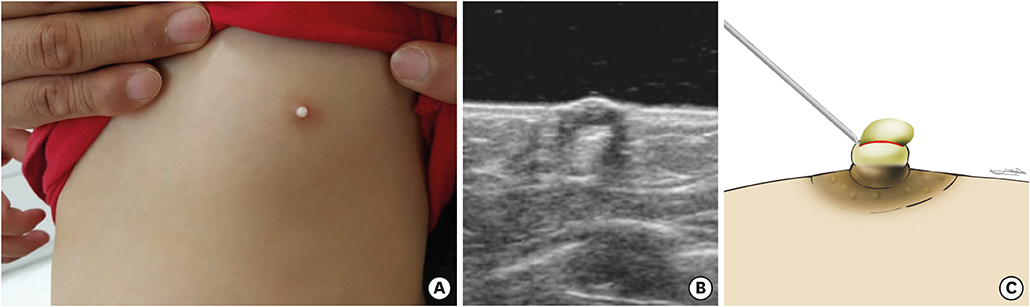

Fig. 2). After the first operation, the lesion appeared to be healed with slight elevation of left nipple, However, 16 months later, the patient revisited our hospital due to recurrence in the form of a 4×1.5 mm milk-colored, central elevation of the nipple. Excision of the lesion-containing capsule was performed with a No. 15 surgical blade in the outpatient clinic (

Fig. 3). After this second operation, she improved without specific complications and had no recurrence within the follow up period of 9 months.

Fig. 3 The recurrent milium of the nipple. (A) Gross finding of patient at recurrence. (B) Second operative procedure: excision.